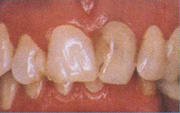

(Mặt sứ) trước điều trị

(Mặt sứ) sau điều trị